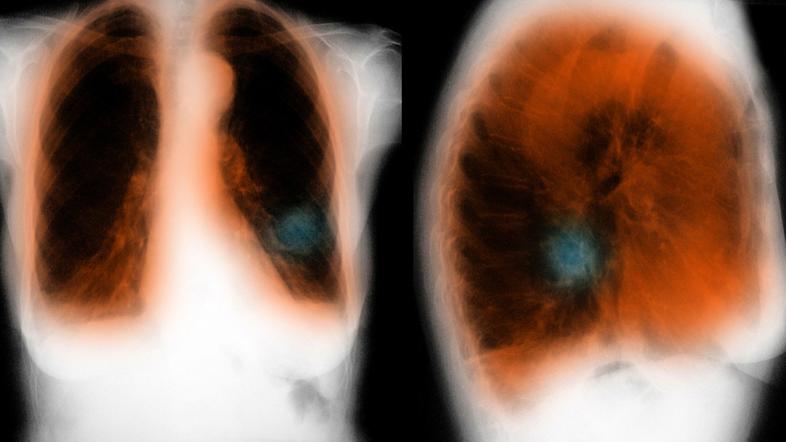

pljuča KOPB

Prepozno odkrita bolezen: Vseh bolnikov s KOPB je v Sloveniji med 50.000 in 100.000. Izmerite si pljučno funkcijo.

pljuča KOPB Težke bolezni Zdravje Alarmantno opozorilo: Ti otroci pozneje v življenju v veliko večji nevarnosti